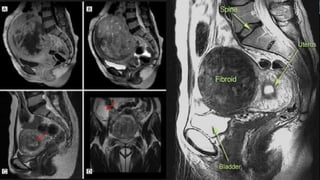

• Magnetic resonance imaging — Magnetic resonance imaging (MRI) is the

most effective modality for visualizing the size and location of all uterine

myomas and can distinguish among leiomyomas, adenomyosis, and

adenomyomas.

• Magnetic resonanceimaging — Magnetic resonance imaging (MRI) is the most effective modality for visualizing the size and location of all uterine myomas and can distinguish among leiomyomas, adenomyosis, and adenomyomas.

MRI MAPPING • Priorto myomectomy, it is very important to detect all the fibroids in the uterus however small and if not removed will lead to higher chances of recurrence. • Ultrasound cannot detect fibroid less than 2 cm i.e seedling fibroids • MRI is superior imaging technique for mapping all the fibroids because it can detect small seedling fibroids also